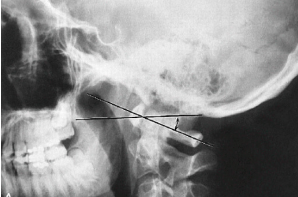

Q what is the name of this measurement? and what is the average + range?

A: Method of Bull

assesses an angle formed by two lines

Chamberlain; from posterior hard palate to posterior foramen magnus

Atlas plane line; second line through midpoints of ANT/POST atlas tubercles

The average angle is 13° and any angle greater than 13° is considered abnormal.